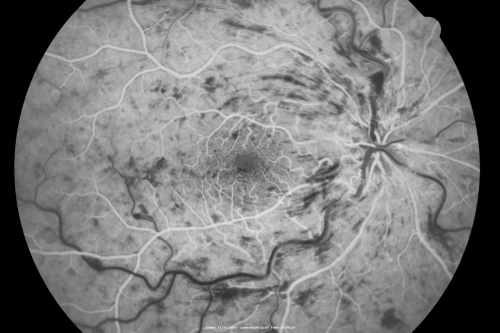

49-year-old woman has central retinal vein occlusion right eye with fluctuating vision for a few month now with OD 20/100. IOP: OD 20

CRVO and CME treated with intravitreal Kenalog 49 Year Old Woman